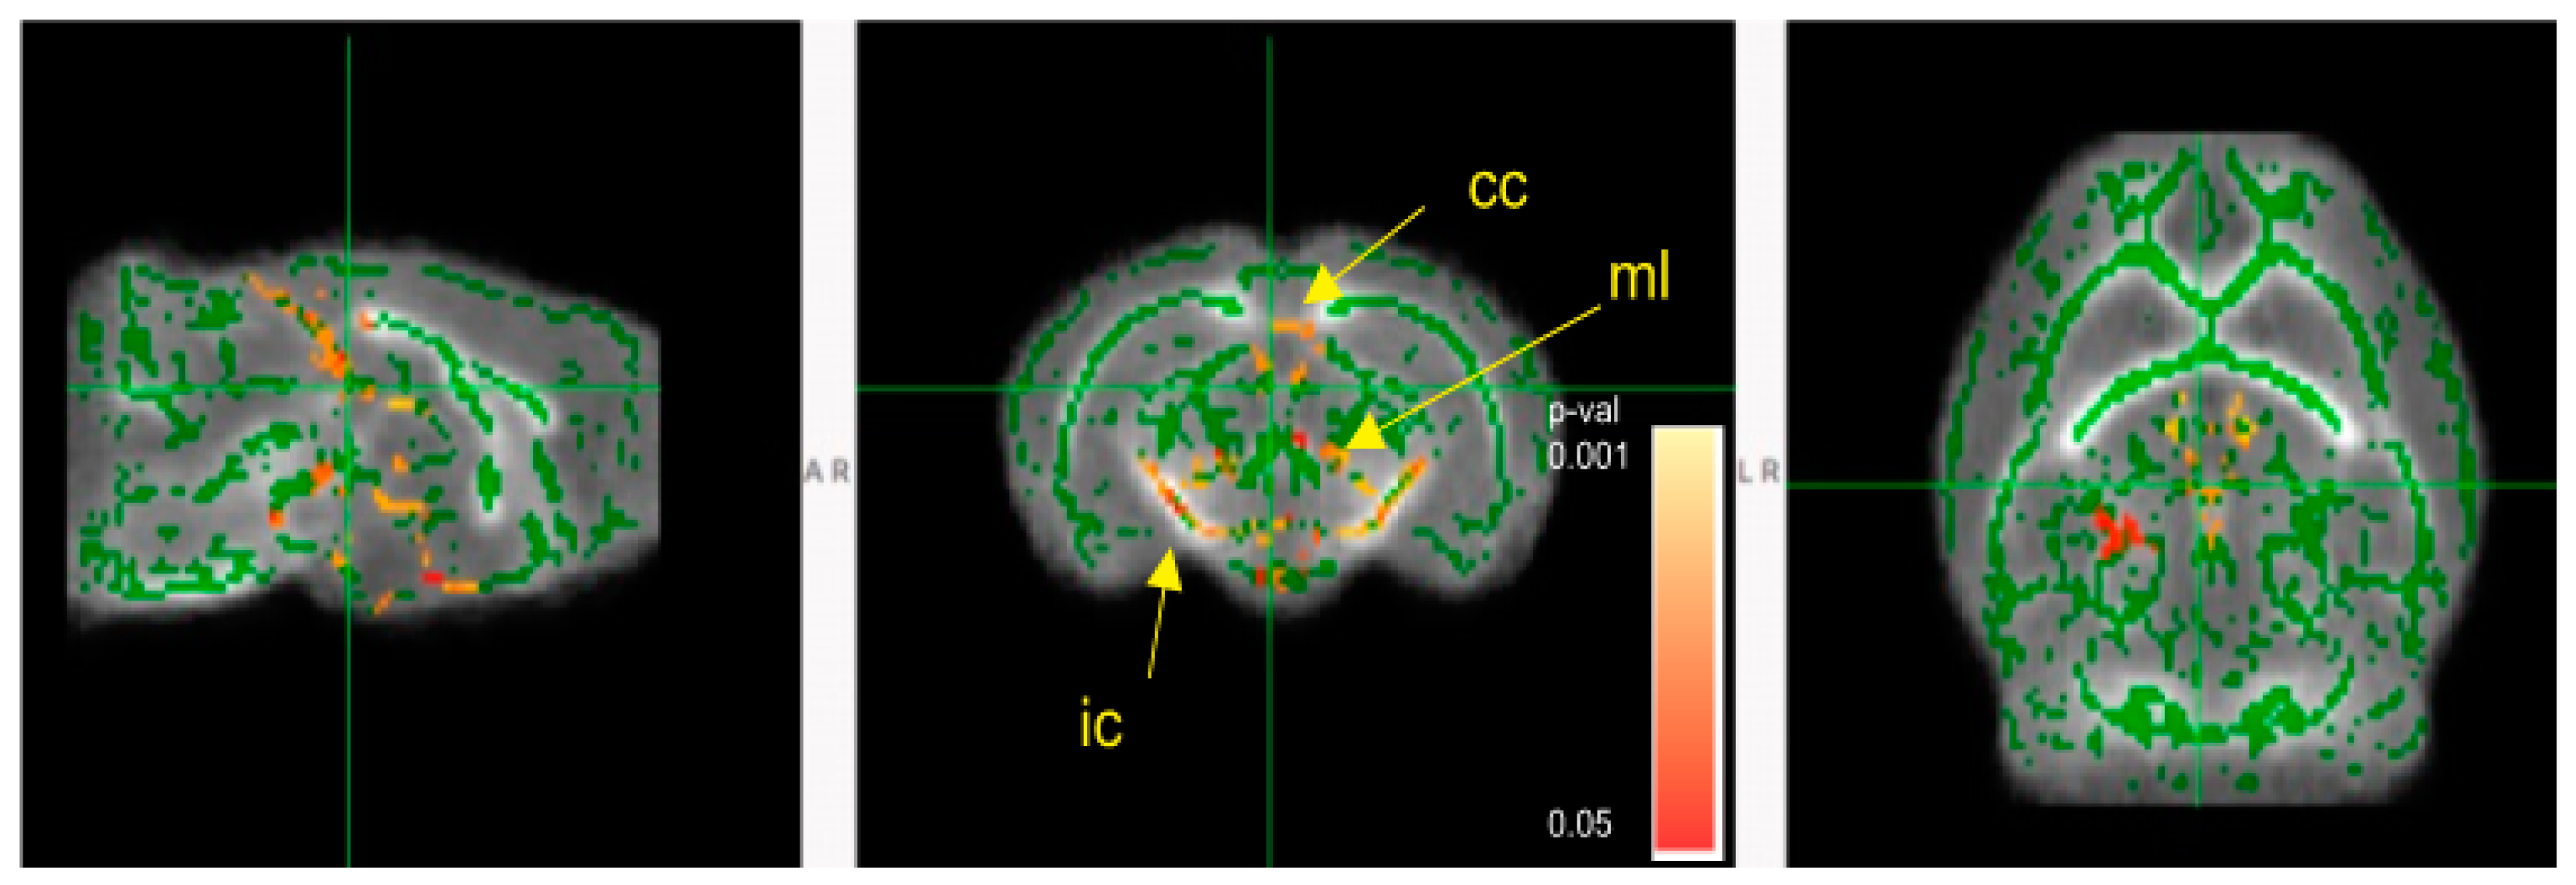

3.5. Mice Colonized with Fecal Samples from Preterm Infants Who Developed NEC Displayed Deficits in Brain Maturation

- Smith, S.M.; Jenkinson, M.; Johansen-Berg, H.; Rueckert, D.; Nichols, T.E.; Mackay, C.E.; Watkins, K.E.; Ciccarelli, O.; Cader, M.Z.; Matthews, P.M.; et al. Tract-based spatial statistics: Voxelwise analysis of multi-subject diffusion data. Neuroimage 2006, 31, 1487–1505. [Google Scholar] [CrossRef] [PubMed]

- Smith, S.M.; Johansen-Berg, H.; Jenkinson, M.; Rueckert, D.; Nichols, T.E.; Miller, K.L.; Robson, M.D.; Jones, D.K.; Klein, J.C.; Bartsch, A.J.; et al. Acquisition and voxelwise analysis of multi-subject diffusion data with tract-based spatial statistics. Nat. Protoc. 2007, 2, 499–503. [Google Scholar] [CrossRef] [PubMed]